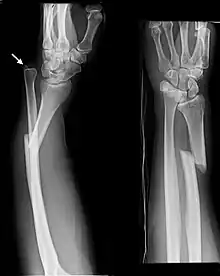

| Galeazzi fracture. Arrow points at the dislocated ulnar head | |

The Galeazzi fracture is a fracture of the distal third of the radius with dislocation of the distal radioulnar joint. It classically involves an isolated fracture of the junction of the distal third and middle third of the radius with associated subluxation or dislocation of the distal radio-ulnar joint; the injury disrupts the forearm axis joint.[1]

The dislocation of ulnar head in Galeazzi fracture dislocation may be dorsal (commoner) or volar (rare) depending on the mechanism of injury. If the fall is on the outstretched hand with forearm in pronation, the dislocation is dorsal, and if forearm is in supination at the time of injury, the dislocation is volar.[2]